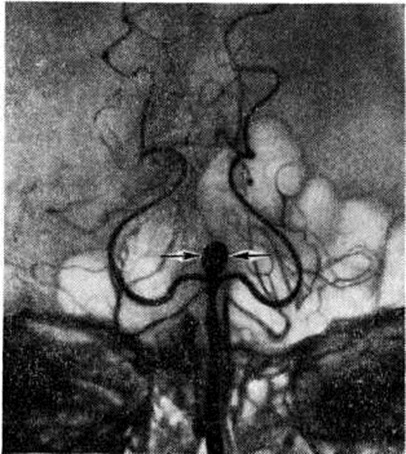

Возникший вскоре после разрыва аневризмы вазоспазм (рисунок 4) сохраняется, как показали ангиографические исследования, до четырёх недель. Обычно спазм захватывает тот сосуд, в котором располагается аневризма. Причины возникновения ангиоспазмов (смотри полный свод знаний) полностью не раскрыты. Некоторые учёные придают значение повышенной чувствительности хеморецепторов сосудистой стенки к постоянно циркулирующим: в крови катехоламинам; другие считают спазмогенным субстратом серотонин, высвобождающийся из тромбоцитов при разрыве аневризм. Не исключено, что высвобождению серотонина способствует простагландин F2a, находящийся в плазме крови и значительно активирующий агрегацию тромбоцитов и выход из них серотонина. В эксперименте показано значительное уменьшение

спазма сосудов при введении эуфиллина или изопротеринола (бета-блокатора). Оба препарата увеличивают содержание циклического аденозинмонофосфата в крови, что уменьшает вазоконстрикцию.